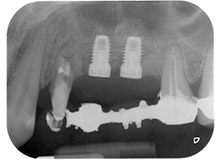

The implants (Restore, Keystone Dental, diameter 3,75 mm, length 8.0 mm) were placed with the implant motor (Figs. 11 and 12).

Bone deficiencies around the implants, at the mesial aspect of tooth 27 and around the buccal root of tooth 24, were filled with xenogeneic bone substitute particles and covered with an absorbable collagen membrane (Bio-Gide, Geistlich Biomaterials) for GBR augmentation (Figs. 13 and 14).

Finally, after periosteal incision, the site was passively sutured with a coronally advanced flap, using 5-0 absorbable suture material (Fig. 15). The postoperative radiograph showed both implants in their correct vertical position (Fig. 16).